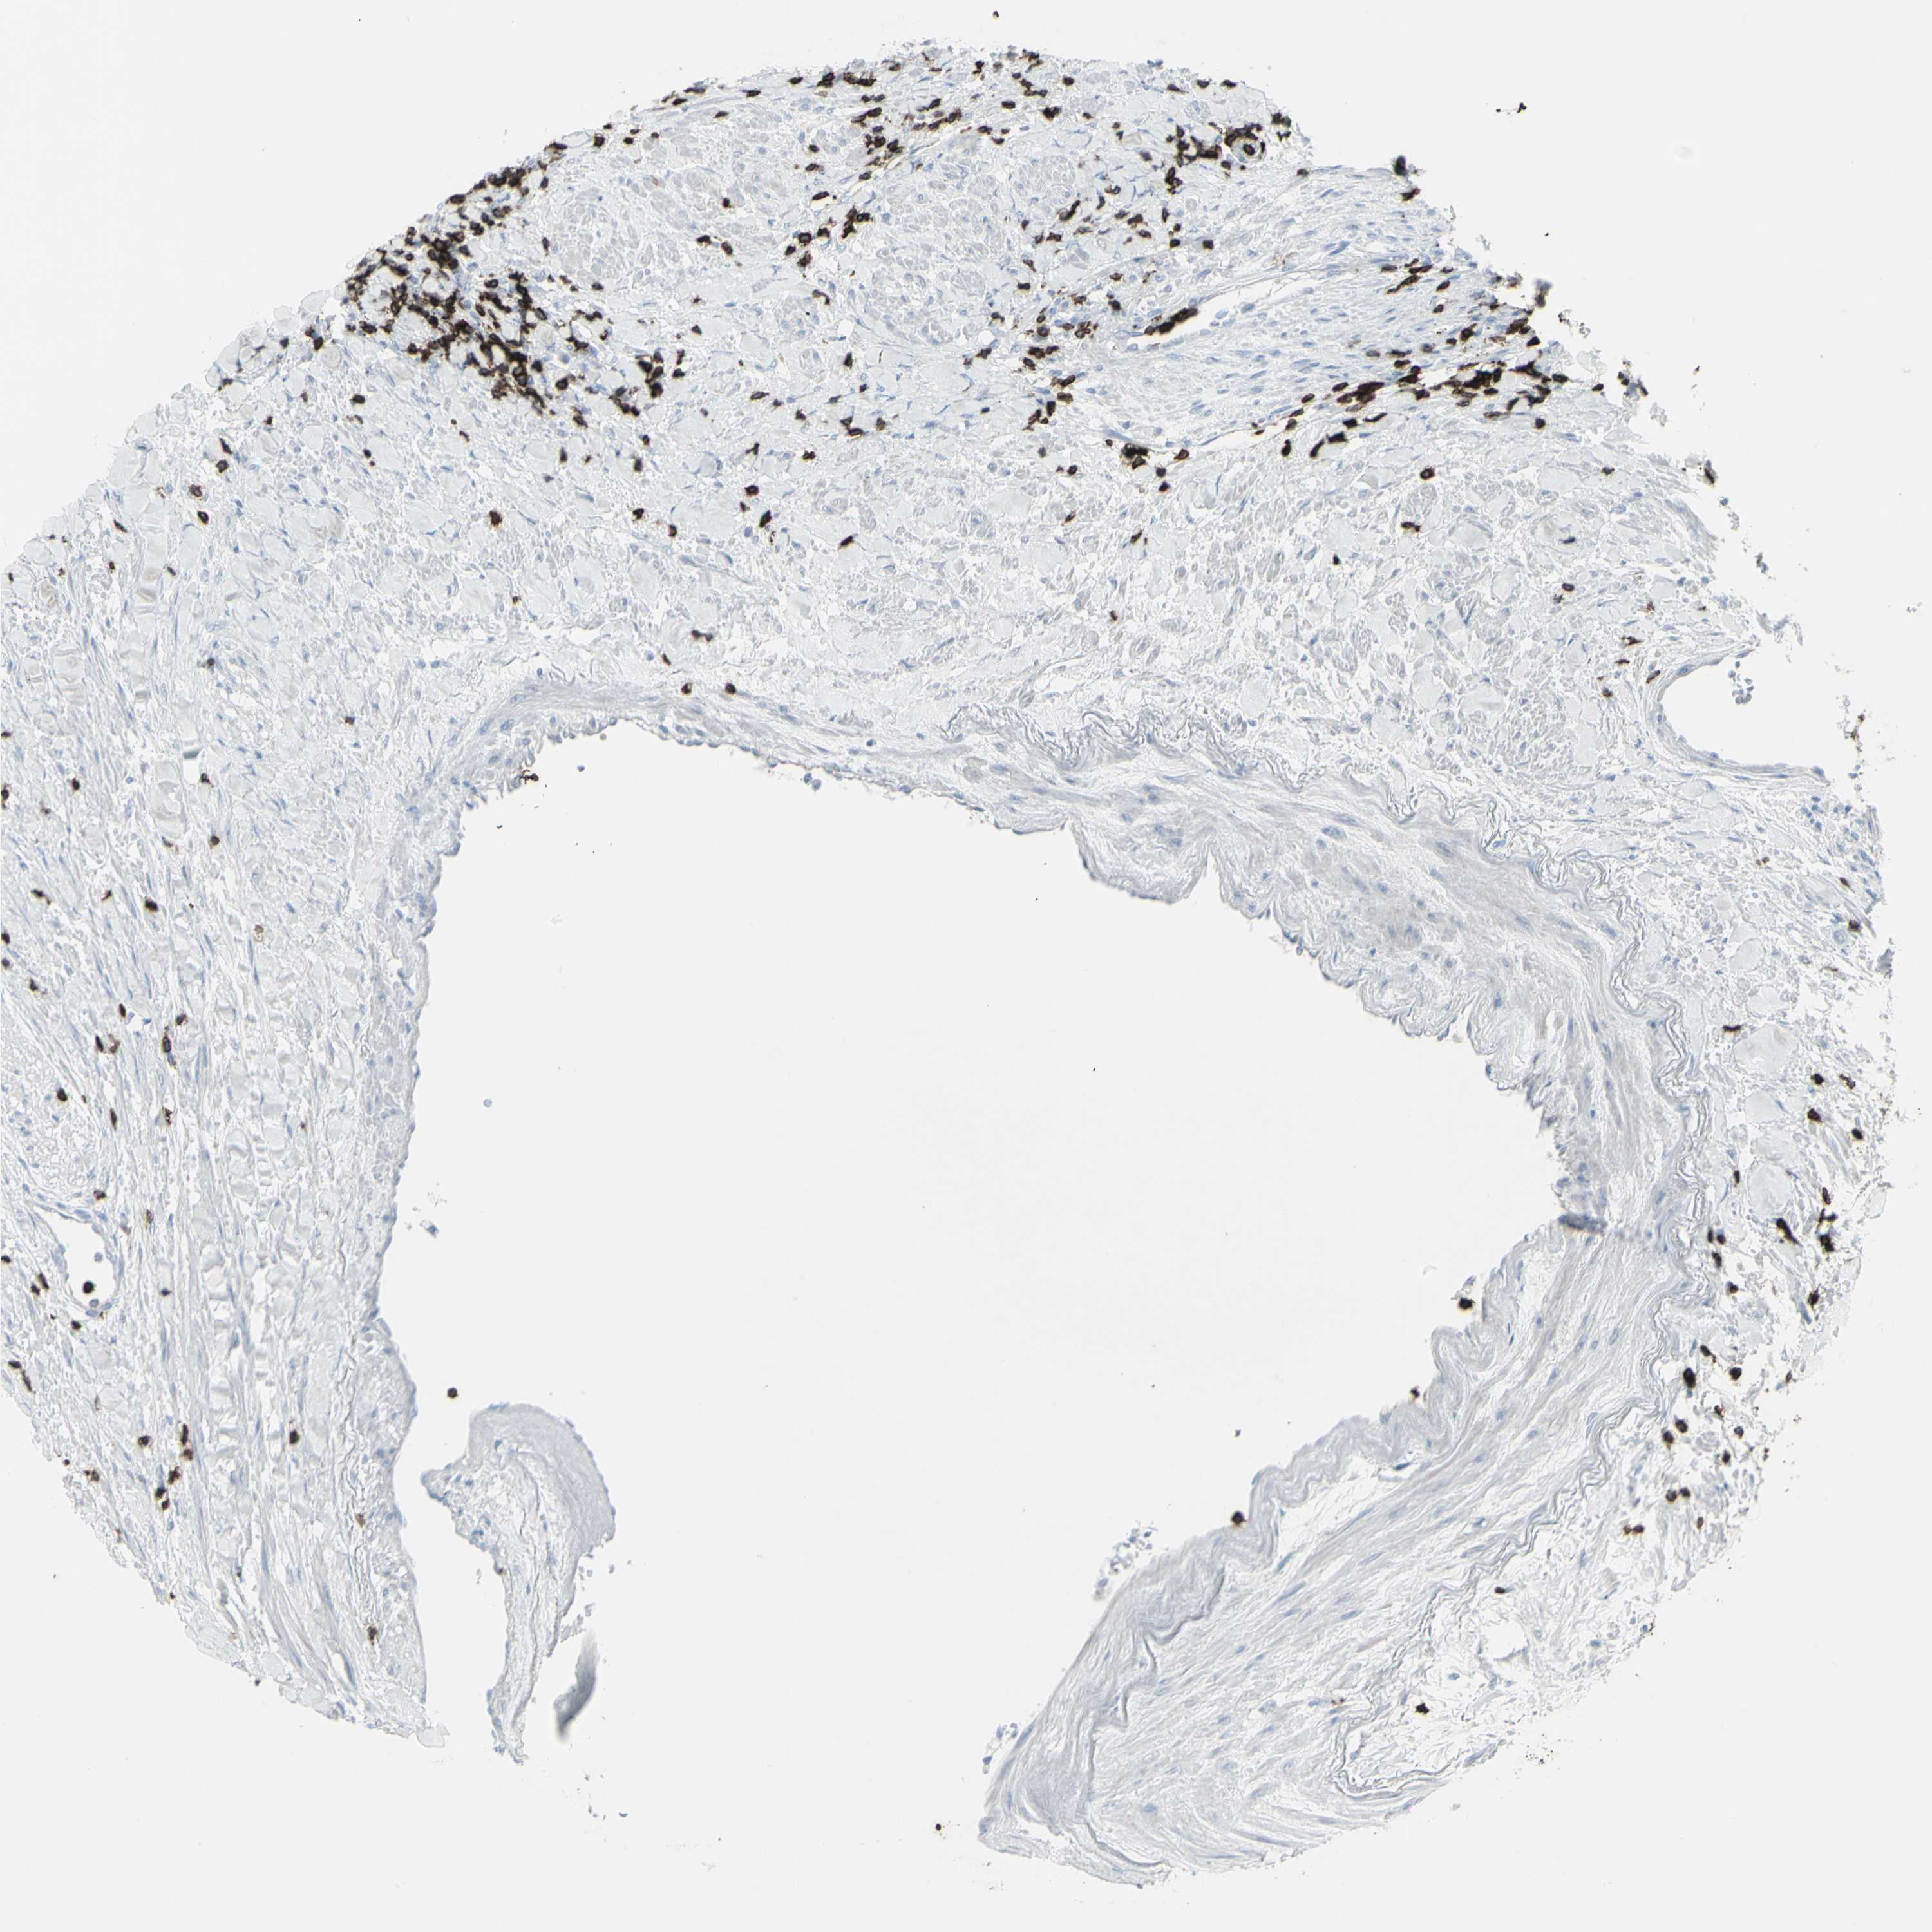

KIDNEY RENAL CLEAR CELL CARCINOMA (VALIDATION) - Interactive survival scatter ploti

The Survival Scatter plot shows the clinical status (i.e. dead or alive) for all individuals in the patient cohort, based on the same data that underlies the corresponding Kaplan-Meier plots. Patients that are alive at last time for follow-up are shown in blue and patients who have died during the study are shown in red.

The x-axis shows the expression levels (FPKM) of the investigated gene in the tumor tissue at the time of diagnosis. The y-axis shows the follow-up time after diagnosis (years). Both axes are complimented with kernel density curves demonstrating the data density over the axes. The top density plot shows the expression levels (FPKM) distribution among dead (red) and alive patients (blue). The right density plot shows the data density of the survived years of dead patients with high and low expression levels respectively, stratified using the cutoff indicated by the vertical dashed line through the Survival Scatter plot. This cutoff is automatically defined based on the FPKM cutoff that minimizes the p-score. The cutoff can be changed by dragging the vertical line or by entering a cutoff value in the square labeled "Current cut-off".

Under the Survival Scatter plot the p-score landscape (black curve; left axis) is shown together with dead median separation (red curve; right axis). Dead median separation is the difference in median mRNA expression between patients who have died with high and low expression, respectively. It is calculated as follows: median FPKM expression of dead patients with high expression - median FPKM expression of dead patients with low expression. This is intended to aid the user in visually exploring custom cutoffs and the associated p-scores and dead median separation.

Individual patient data is displayed and can be filtered by clicking on one or more of the category buttons on the top of the page. Categories describing expression level and patient information include: high, low, alive, dead, female, male and tumor stages. The scale of the x-axis can be toggled between linear and log-scale by clicking on the "x log" button. Mouse-over function shows TCGA ID, patient information and mRNA expression (FPKM) for each patient.

& Survival analysisi

Kaplan-Meier plots summarize results from analysis of correlation between mRNA expression level and patient survival. Patients were divided based on level of expression into one of the two groups "low" (under cut off) or "high" (over cut off). X-axis shows time for survival (years) and y-axis shows the probability of survival, where 1.0 corresponds to 100 percent.

CD247 is not prognostic in Kidney Renal Clear Cell Carcinoma (validation)

: 14.81

Average pTPM 11.7

Number of samples 100